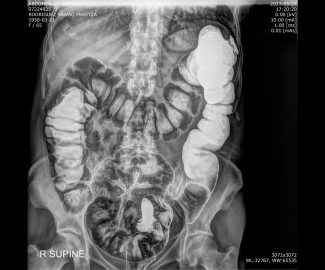

Especialista en diagnóstico por imágenes con más de 25 años de experiencia en el campo del ultrasonido y radiología digital. Trabajamos con equipos de alta tecnología garantizando la calidad y seguridad de nuestros diagnósticos, pues nuestra prioridad es la salud, bienestar y satisfacción de nuestros pacientes.

Sabemos que visitar un centro médico a veces genera nervios. Por eso, hemos creado un ambiente cálido, moderno y 100% seguro para ti. Desde nuestra cómoda sala de espera hasta nuestras áreas de ecografía, mamografía y rayos X, cada rincón está equipado con tecnología de última generación y diseñado para que te sientas en confianza.